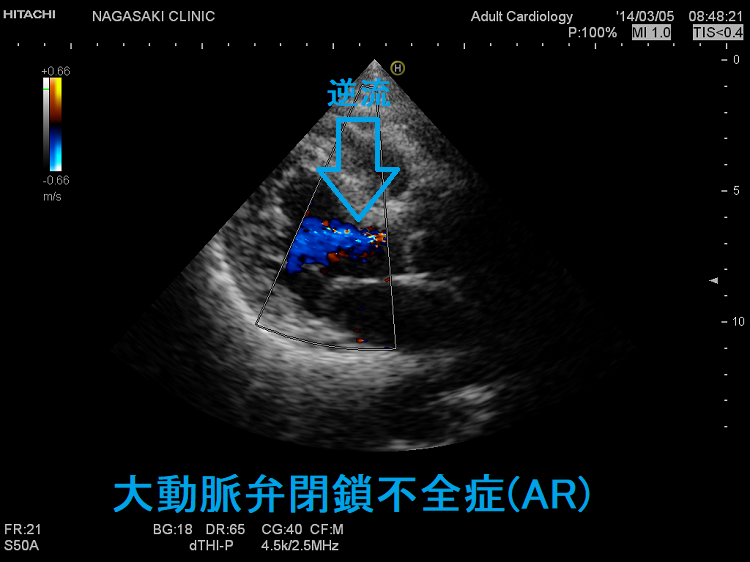

大動脈弁閉鎖不全症(AR)では、

- 逆流により左室血液量が増加し、相対的な大動脈弁狭窄症(AS)を引きおこす

- 胸骨左縁第3 肋骨を最強点とする拡張期雑音を聴取

脈拍が急激に大きくなり、ついで急激に小さくなる速脈は循環血液量多くなる甲状腺機能亢進症、大動脈弁閉鎖不全症(AR)でみられます。

甲状腺異常と大動脈弁閉鎖不全症(AR)を合併する疾患として、

- 先端巨大症(成長ホルモン産生下垂体腺腫)[J Endocrinol Invest. 2020 Mar;43(3):279-287.]

- ターナー症候群

- チロシン(アミノ酸の1つ)代謝異常のアルカプトン尿症(アルカプトン尿症と甲状腺)